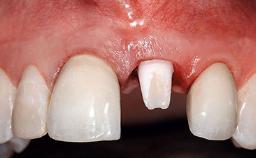

Replacement of an Upper Right Central Incisor with Root Resorption: Ridge Preservation, Delayed Placement of an NC Bone Level Roxolid Implant

A 32-year-old female Caucasian patient with a compromised maxillary right central incisor was referred to us by a general dentist. Her chief complaints were discomfort and mobility of tooth 11 with unsatisfactory esthetics due to discoloration. The patient reported a previous trauma, some years earlier, as the origin of pathology on the afflicted tooth. Anamnesis was negative for any other dental or periodontal pathology in the remaining dentition. The patient did not take any medication and reported to be a light smoker (5–10 cigs/day). She had high esthetic expectations of her treatment. The extraoral examination revealed a high smile line with full exposure of her maxillary teeth and surrounding soft tissue in the area between the second premolars.

Prosthesis Type FDP

Lip Line No exposure of papillae Exposure of papillae Full exposure of mucosa margin